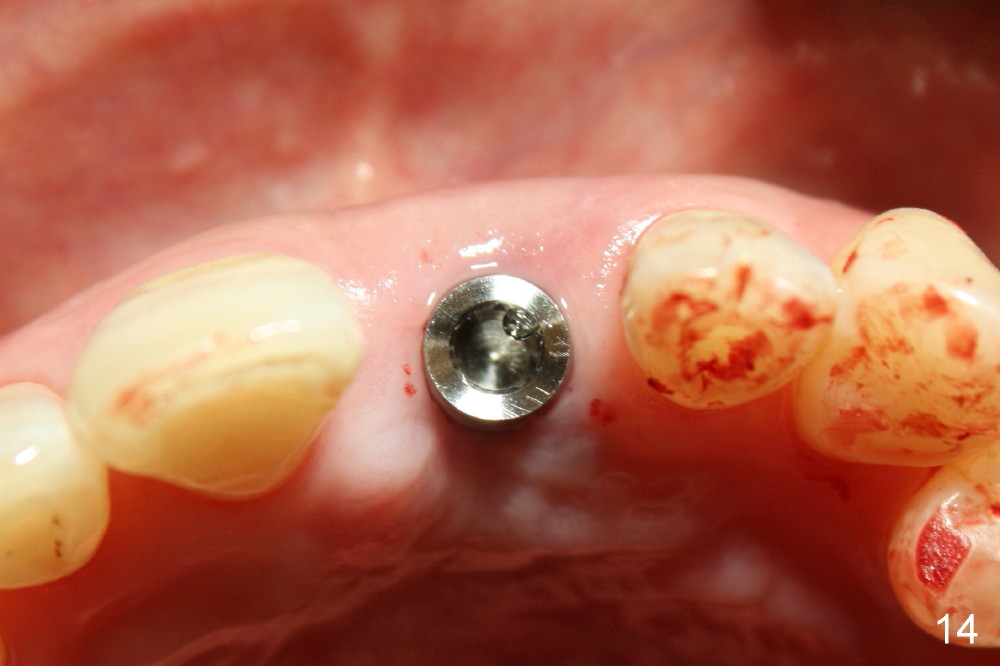

A 60-year-old lady had an abscess mesial to #9 six years ago (Fig.1,2 <), treated as a perio lesion by laser (Fig.3) and osseous surgery without bone graft (Fig.6, followed by CT exam revealing semi-circumferential bone loss (Fig.4,5). When the perio treatment failed, attention was paid to endo aspect (Fig.7-9). In fact the pulp was found to be vital when access to root canal therapy was made. As expected, the treatment failed again. The palatal fistula persisted. The infection was suspected to be a source of remote immediate implant site (#30). The tooth #9 was extracted. It appears that there is a semilunar crack line in the linguomesial root (Fig.12). When the socket healed 2 weeks post extraction (Fig.10), the #30 buccal defect was debrided with bone graft. There was no bone resorption 4 weeks post extraction (Fig.11); a 4.5x17 mm implant was placed (Fig.13-15). An immediate provisional was fabricated (Fig.16-18). Fig.19,20 were taken 3 months post implantation and 7 months post cementation, respectively. Dense bone forms around the implant coronally 4 years 5 months post cementation (Fig.21), while the gingiva is healthy palatally (Fig.22) and buccally (Fig.23).